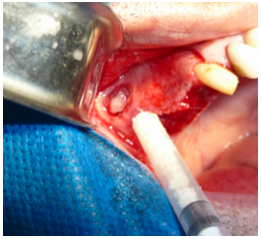

Após a osteotomia é utilizada a ponta em forma de “pata de elefante” para promover o descolamento da membrana sinusal da tábua óssea vestibular e facilitar o descolamento e afastamento da membrana (figura 5).

Após o procedimento de afastamento da membrana (figura 6), é realizado o preparo dos nichos cirúrgicos para a instalação dos implantes, que pelos estudos imaginológicos prévios (Rx panorâmico e tomografia computadorizada), foi possível verificar que seria possível a execução da cirurgia em um tempo cirúrgico, ou seja, da realização do procedimento de elevação do soalho do seio maxilar com a instalação simultânea dos implantes.